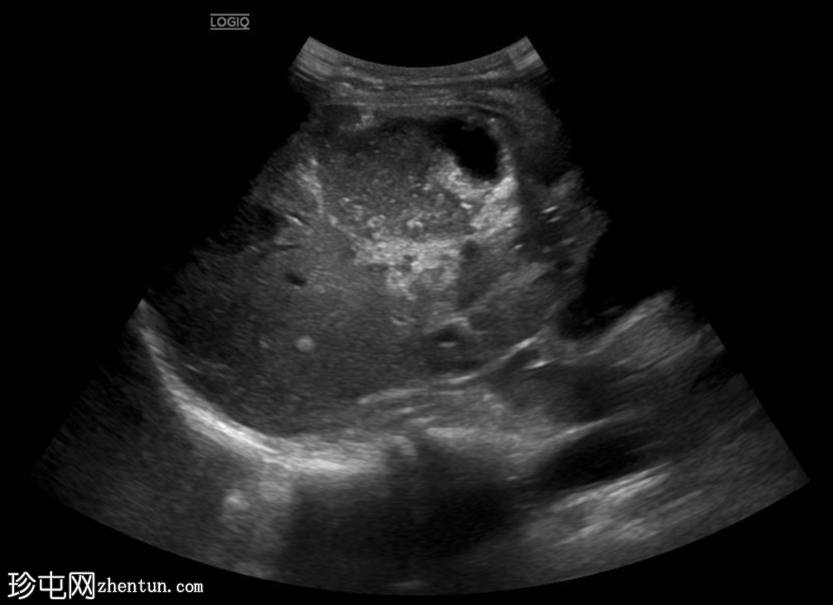

超声检查

纵向

位于肝段VIII中心的异质性肿块,其特征为不规则的高回声边缘、内部粗钙化以及中心低回声至无回声的液-液平面。还可见多个较小、边界清晰的高回声卫星灶。